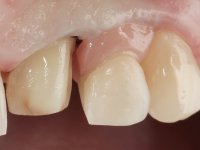

• Reabitação dos dentes Incisivos Centrais Superiores com facetas de cerâmica feldspática.

O tratamento iniciou-se com a re -preparação do coto do espigão falso coto fundido, com o objetivo de colocar as linhas de acabamento cervical com uma localização intra-sulcular e simultaneamente confecionar uma coroa provisória adaptada. Com um tratamento ortodôntico muito simples, fechou-se o diastema entre os incisivos centrais superiores e estabilizou-se esta posição com um arame colocado na superfície palatina dos centrais, funcionando como contenção. Posteriormente procurou-se fazer uma tração ortodôntica lenta do dente 2.2 com o intuito de diminuir, ainda que muito ligeiramente a perda óssea vertical nessa zona. Finalizada a tração, foi feita a extração do dente 2.2 e a zona foi reabilitada provisoriamente com uma coroa de resina composta colada aos dentes adjacentes. Foi colocado um implante dentário na zona do dente 2.2 sendo novamente colada a coroa provisória em resina, reabilitando provisoriamente a paciente durante o período de osseointegração. No dente 1.3 foi feita uma gengivectomia com bisturi elétrico, com a intenção de subir o nível cervical do 1.3 conseguindo uma maior harmonia com o dente 2.3. Estabilizados os tecidos moles, foi feita uma impressão com a técnica de moldeira aberta, utilizando silicones de adição de consistência “putty” e “light”. A recolha da cor, tanto da componente dentária como dos tecidos moles foi feita pelo ceramista no consultório.  No laboratório as impressões foram passadas a gesso e deram origem a modelos de trabalho que foram devidamente analisados. Foi decidido confecionar um “abutment” metalo-cerâmico aparafusado sobre o implante. Este “abutment” foi fundido com uma liga nobre e posteriormente revestido a cerâmica coronária e gengival. Dada a inclinação do implante o aparafusamento condicionou de forma inevitável a saída do orifício do parafuso pela superfície vestibular. No sentido de esconder esta situação, o desenho do “abutment” já foi idealizado com a intenção de acomodar na superfície vestibular a colagem de uma faceta feldspática. Este “abutment” foi provado em boca e foram feitos ajustes no componente cerâmico gengival. A sua adaptação aos tecidos moles foi feita tanto de forma subtrativa, com broca, como de forma aditiva, acrescentando resina composta de tonalidade gengival. Este acrescento de resina seria orientador do ceramista na colocação final da cerâmica de tonalidade gengival. A coroa que reabilitaria o dente 1.3 foi cimentada nesta consulta de prova com cimento de ionómero de vidro reforçado com resina composta. Finalizado o trabalho em laboratório da faceta sobre o 1.2 e o “abutment” e a faceta para o implante este foi colado em boca, após a colocação do isolamento absoluto. O trabalho satisfez plenamente a paciente. Durante oito anos a paciente foi seguida regularmente, mostrando-se agradada com o tratamento efetuado, no entanto começou a mostrar interesse em intervir esteticamente nos incisivos centrais superiores. Decidida a segunda fase da nossa intervenção, foi feita a preparação dentária dos dentes 1.1 e 2.1 para a colocação de duas facetas feldspáticas. Particular cuidado foi tido na preparação inter-proximal distal junto ao “abutment” do implante. Foi preciso avaliar muito pormenorizadamente o eixo de inserção da faceta em relação ao “abutment”. As facetas feldspáticas foram confecionadas em laboratório e posteriormente coladas em boca após a colocação de isolamento absoluto. Um ano após, iniciamos a nossa terceira fase de tratamento, após a faceta colada no dente 2.1 ter fraturado. A preparação dentária foi feita sobre a faceta colada, procurando estender mais para palatino o interface inter-proximal distal. O objetivo seria passar para mais palatino do ponto de contacto o interface faceta-dente. O preparo dentário do dente 1.2 também foi muito reduzido, limitando-se a criar um eixo de inserção. Após confecionadas a coroa total e a faceta em laboratório foram coladas em boca. Primeiro foi colada a coroa utilizando-se um isolamento relativo com teflon, posteriormente foi colada a faceta após a colocação do isolamento absoluto. Na coroa utilizei este tipo de isolamento para evitar a utilização de grampos. Seria difícil de aplicar pela forma e dimensão do dente e agressivo para os tecidos moles. Após a colagem foi avaliada a integração oclusal do trabalho.